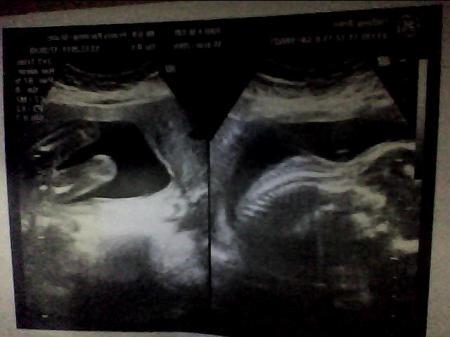

hoffe du kannst es erkennen...

Bild zu

Ich hoffe du erkennst was.